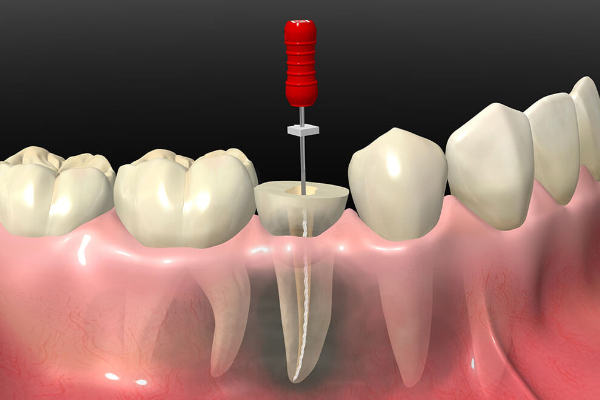

治療方法:不良補綴物を除去し再根管治療を行った後、深い歯周ポケットに対して歯周外科治療を行った。歯肉の安定の後歯冠修復治療を行った。

複雑な根管治療形態や歯根破折の際は治癒しない場合があります。

根管治療中に痛みや腫れが生じる場合があります。

通常の根管治療で治癒しない場合は外科的治療や抜歯となる場合があります。